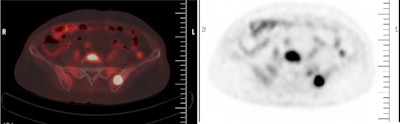

To elucidate the issue, the group compared the methods in retrospective data from 146 patients ages 18 to 80 of either gender with a confirmed diagnosis of DLBCL on tissue biopsy. All patients had bone biopsies and underwent whole-body F-18 FDG-PET/CT scans (Gemini TF 16, Philips) from the base of the skull to the mid-thigh.

According to the analysis, 47 (32.19%) cases had bone marrow involvement identified on bone marrow biopsies and 50 (34.2%) cases had bone marrow involvement seen on PET/CT scans. There were six false positives on PET/CT but not on biopsy and three false negatives on biopsy but not on PET/CT. The overall diagnostic accuracy of PET/CT was 93.84%.